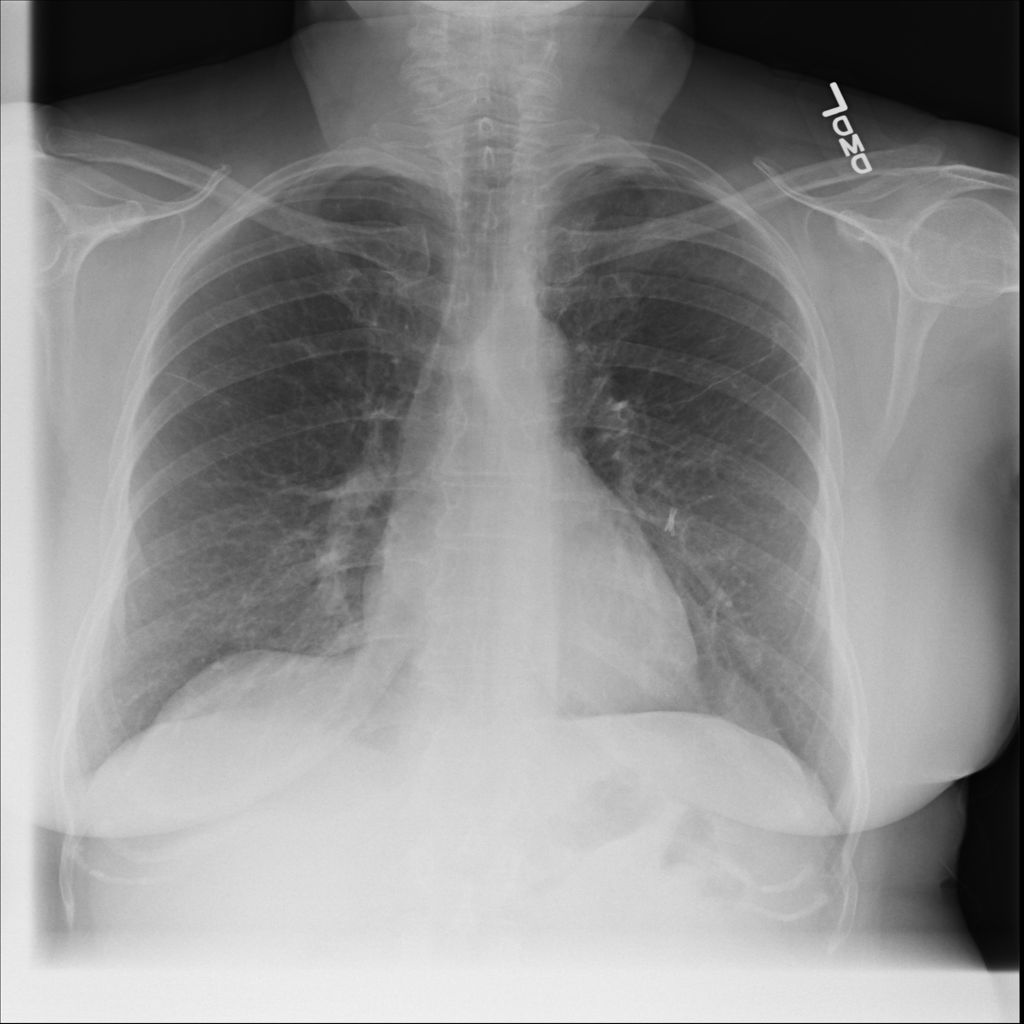

PAT-E960 · IMG-002Fibrosis

PAT-E960 · IMG-002

PA